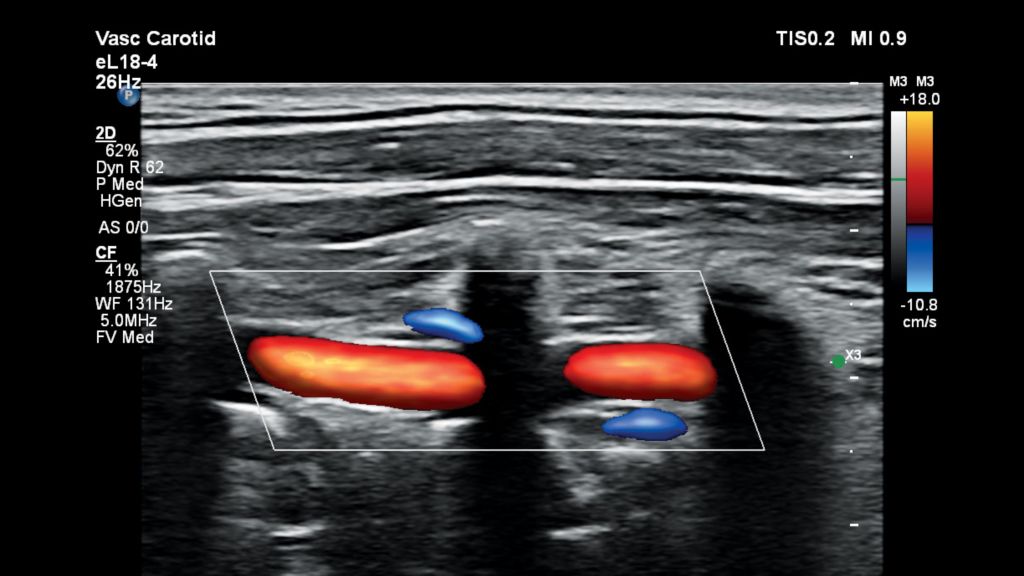

• Carotid

Carotid-Flow Viewer represents vascular flow topography with a 3D-like appearance